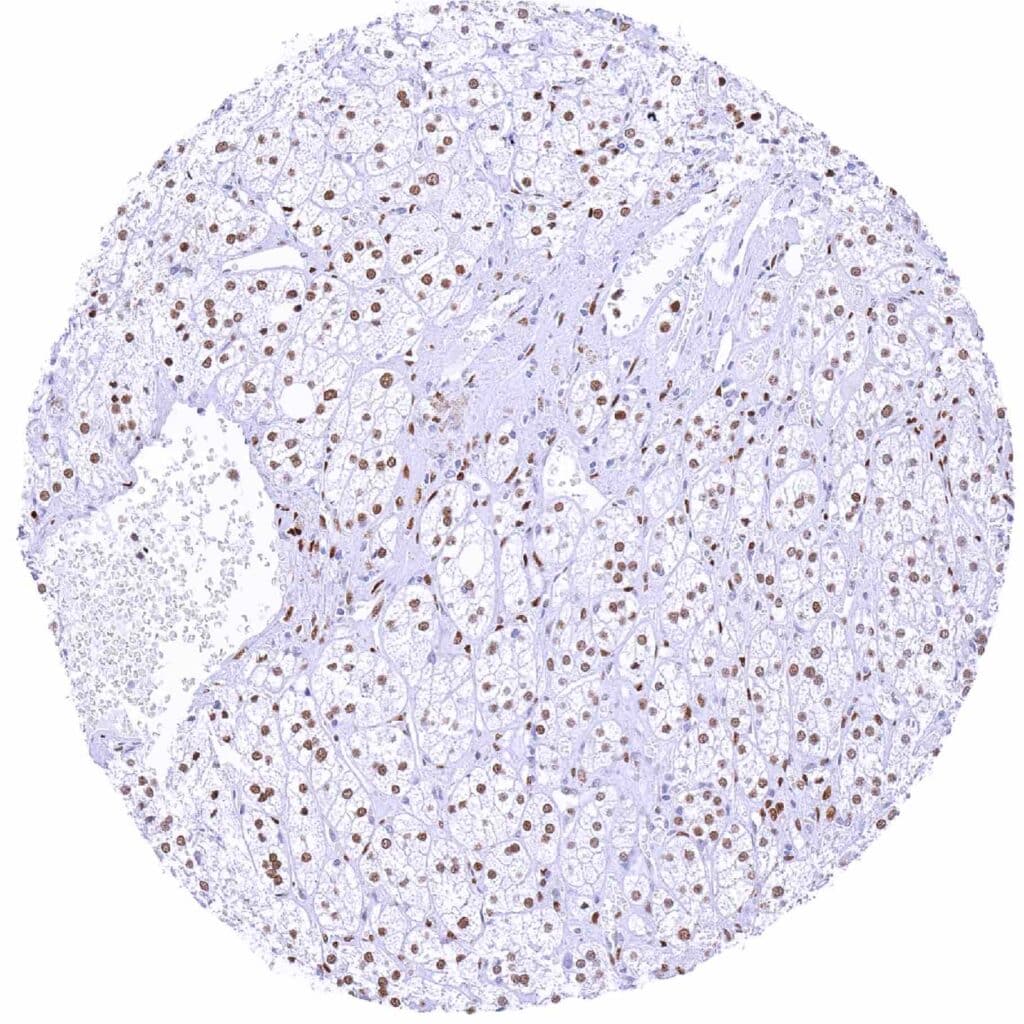

Liver – Nuclear NFIX staining is largely absent in hepatocytes. NFIX staining is only seen in stromal cells